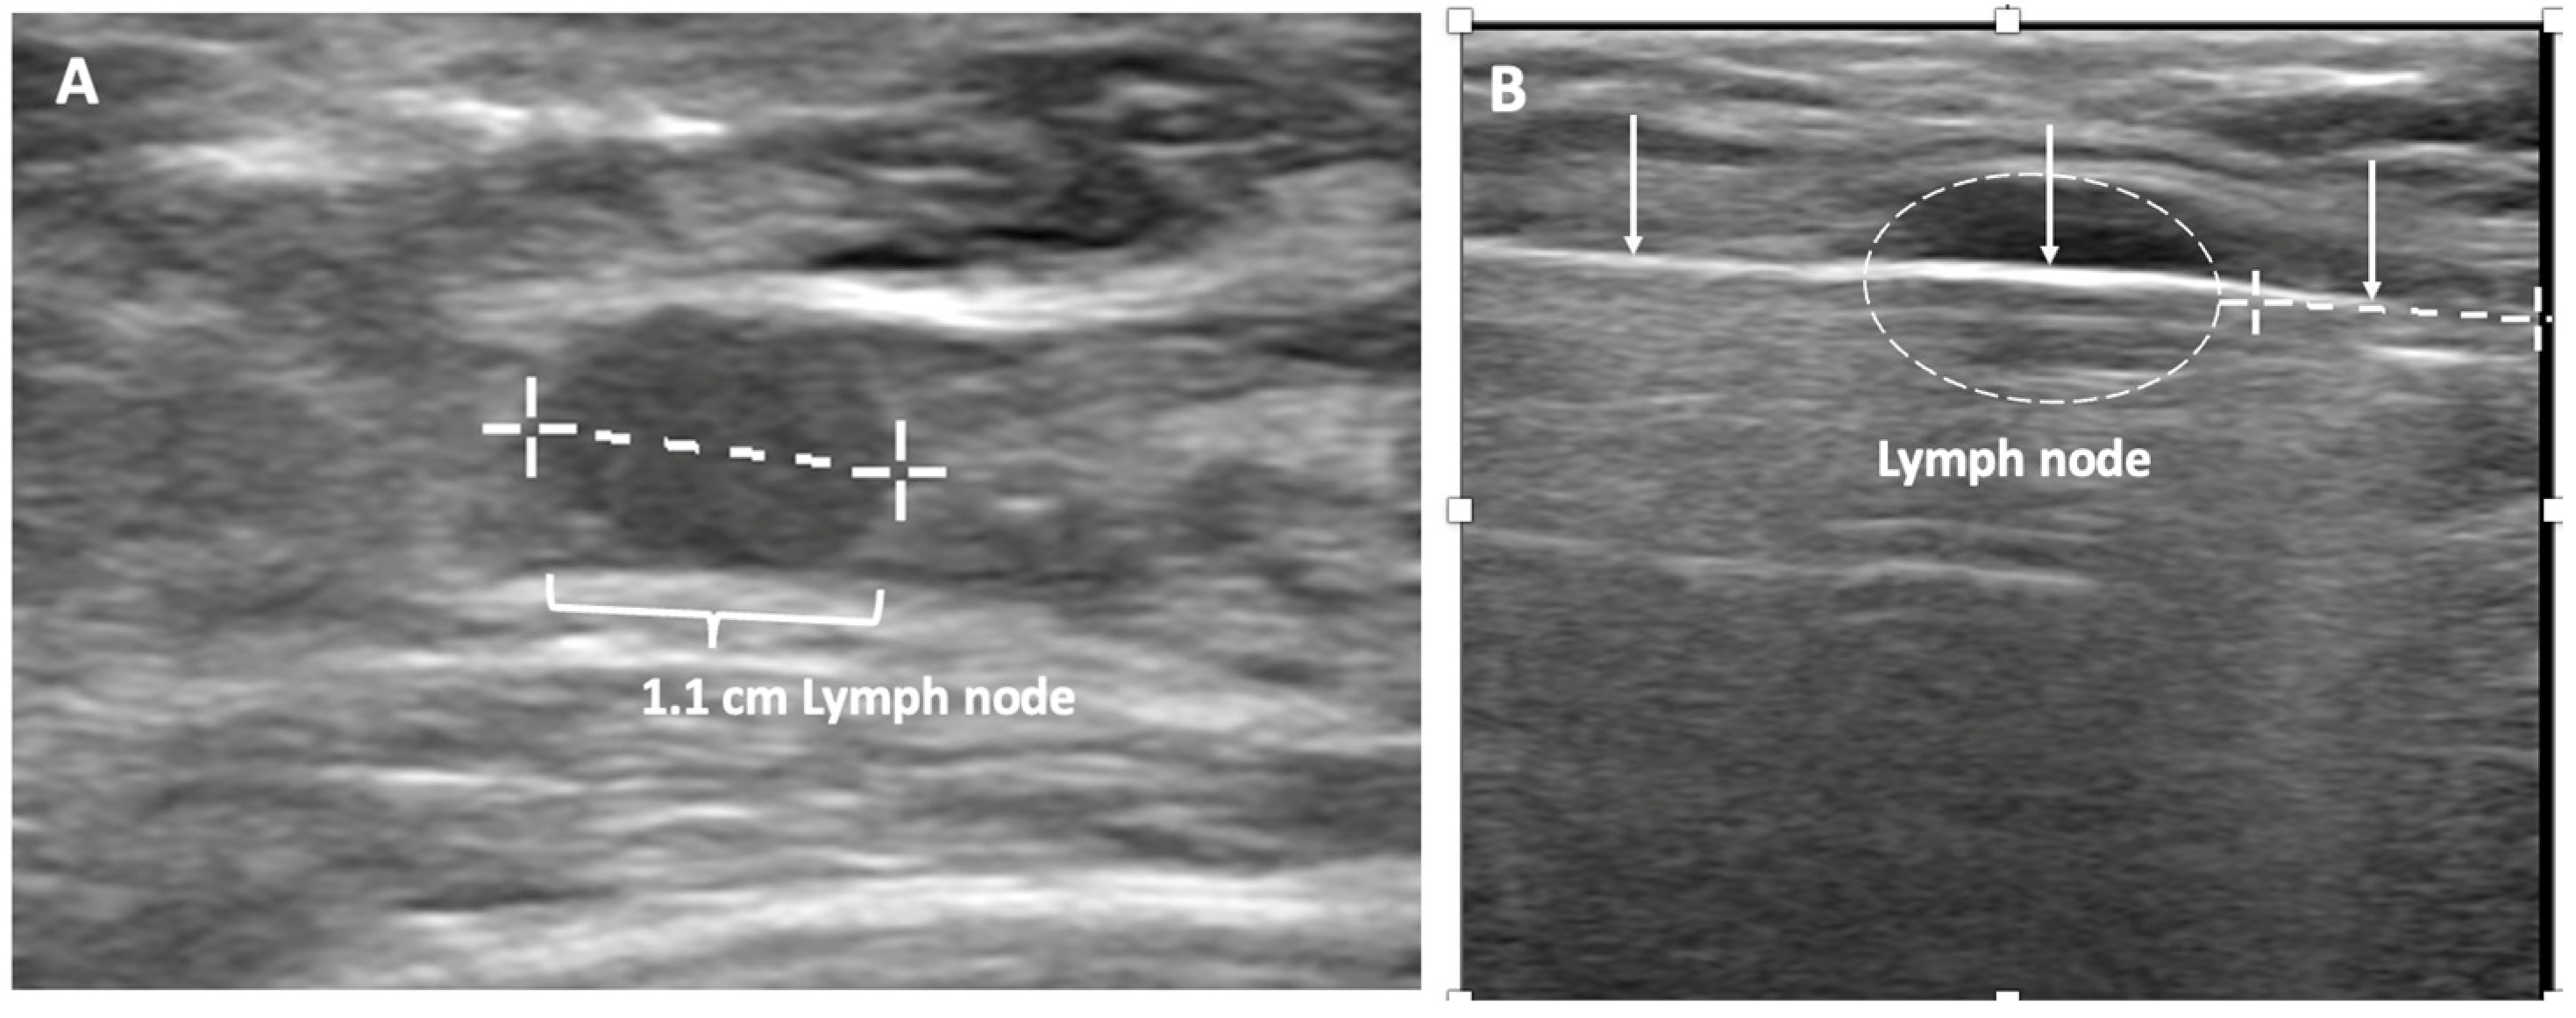

Ultrasound of the axilla. Axillary ultrasound permits the detection of abnormal appearing lymph nodes that might not be detected on physical examination, mammography, or breast MRI. Axillary ultrasound is the most sensitive imaging study for the detection of subtle changes in the shape or thickness of a lymph node cortex that might indicate the presence of lymph node metastasis (Figure 3). Detection of suspicious lymph nodes determines clinical cancer stage and requires a specific plan to manage the possibility of lymph node metastasis.

Figure 3.

Hash marks outline abnormal appearing axillary lymph node measuring 1.5 cm in maximal diameter. Paired “+” marks indicate the span of a 0.4 cm area of focal cortical thickening that is suspicious for a metastatic deposit within the lymph node.

Despite the surgical advancements to minimize the burden of lymph node surgery, some patients with positive lymph nodes continue to refuse lymph node surgery. In the context of patient centered care, some patients with limited nodal disease may be considered for lymph node cryoablation in lieu of surgery (Figure 17). Lymph node cryoablation entails several important considerations. Unlike cancers in the breast, the encapsulated nature of lymph nodes obviates the need for cryoablation of a wide surgical margin. Thus, cryoablation freeze times may be cut short when the dimensions of the iceball extend 5 mm beyond the lateral edges of the lymph node. However, lymph node cryoablation is not without hazard. Although lymph node cryoablation is a minimally invasive procedure, the elongated shape of the oval iceball typically causes the cryoablation zone of necrosis to extend 10–15 mm beyond the near and far edges of the lymph node, which can inadvertently cause cryoablation or injury to adjacent nodes, vessels, or nerves. Furthermore, since cryoablation does not permit axillary reverse mapping, lymph node cryoablation is comparatively less targeted and potentially more morbid than selectively removal of grossly abnormal axillary lymph nodes.

Figure 17.

(A) shows a grossly abnormal 1.1 cm axillary lymph node prior to insertion of cryoprobe. (B) shows an abnormal lymph node (outlined with hash marks),the cryoprobe traversing the lymph node (white line indicated by arrows), and projection of the cryoprobe tip beyond the distal end of the lymph node (linear hash marks) prior to beginning first freeze cycle.